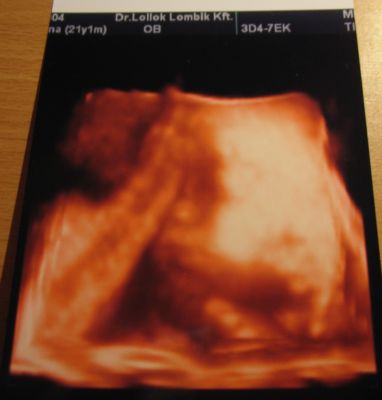

A mellső fali lepény a pocakod eleje....

Ezért is kell jobban vigyázni...

Úgy tudom, (bár én amúgy sem..) hogy mellső fali lepénnyel még a kismamatorna sem javasolt.